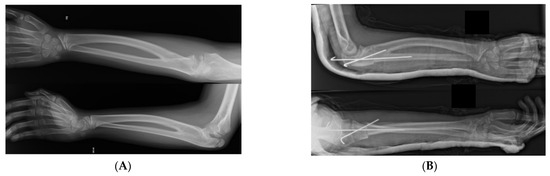

Surgery is a common treatment for symptomatic patients with CRUS (Figure 1), but it is not required for most patients unless they have limitations of daily life activities. Mild deformity, minimal functional deficit (<60° of pronation), and adaptations developed for activities are contraindications for surgical procedures [3]. However, surgical treatment would be desirable in bilateral congenital radioulnar synostosis (CRUS) or in patients with a forearm fixed in more than 60° of pronation. The optimal age for surgical treatment is before school age, when the robust periosteum can support the cut radius and facilitate callus formation; thus, nerves and blood vessels can tolerate torsional deformity, avoiding vascular and postoperative complications [3,23].

Figure 1.

(A) Bilateral congenital radioulnar synostosis. Preoperative X-ray. (B) Osteotomy through the synostosis going simple and easy to fix with 2 KW. Postoperative X-ray.